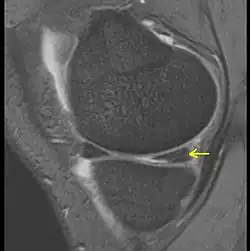

Anders sieht es bei einem Meniskusriss (Meniskusruptur) aus. Innenmeniskusverletzungen (also des Meniscus medialis) sind wesentlich häufiger als die des Außenmeniskus. Die Risse werden nach ihrer Verlaufsrichtung in Längsriss, Radiärriss oder Schrägrisse (Lappenriss) eingeteilt. Bezüglich der Raumebene unterscheidet man Vertikalrisse und Horizontalrisse. Sonderformen sind komplexe Risse, der Korbhenkelriss und ein „flipped meniscus“.[3] Die Diagnose erfolgt durch klinische Untersuchung, Kernspintomographie und Arthroskopie (Gelenkspiegelung).